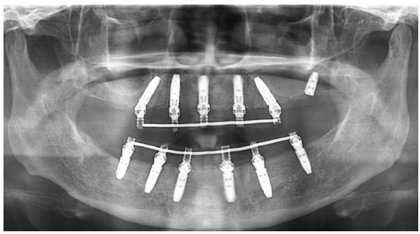

治疗结果:术后3个月全景片显示种植体骨结合良好(图14)。26牙行二期手术,就位复合基台,戴入保护帽。两周后,取下临时修复体,制取上下颌硅橡胶印模,利用临时修复体交叉上

架转移患者颌位关系。设计数字化桥架(图15),切削铝制支架。试戴铝制支架,拍摄全景片显示支架被动就位良好(图16)。按照铝制支架切削纯钛支架,上聚合瓷,患者右侧咬合空间不足,设计金属

术后一年随访:拍摄全景片显示种植体周围骨结合良好,边缘骨高度稳定(图19)。义齿外形无变化,下颌义齿前牙区舌侧面见牙结石。